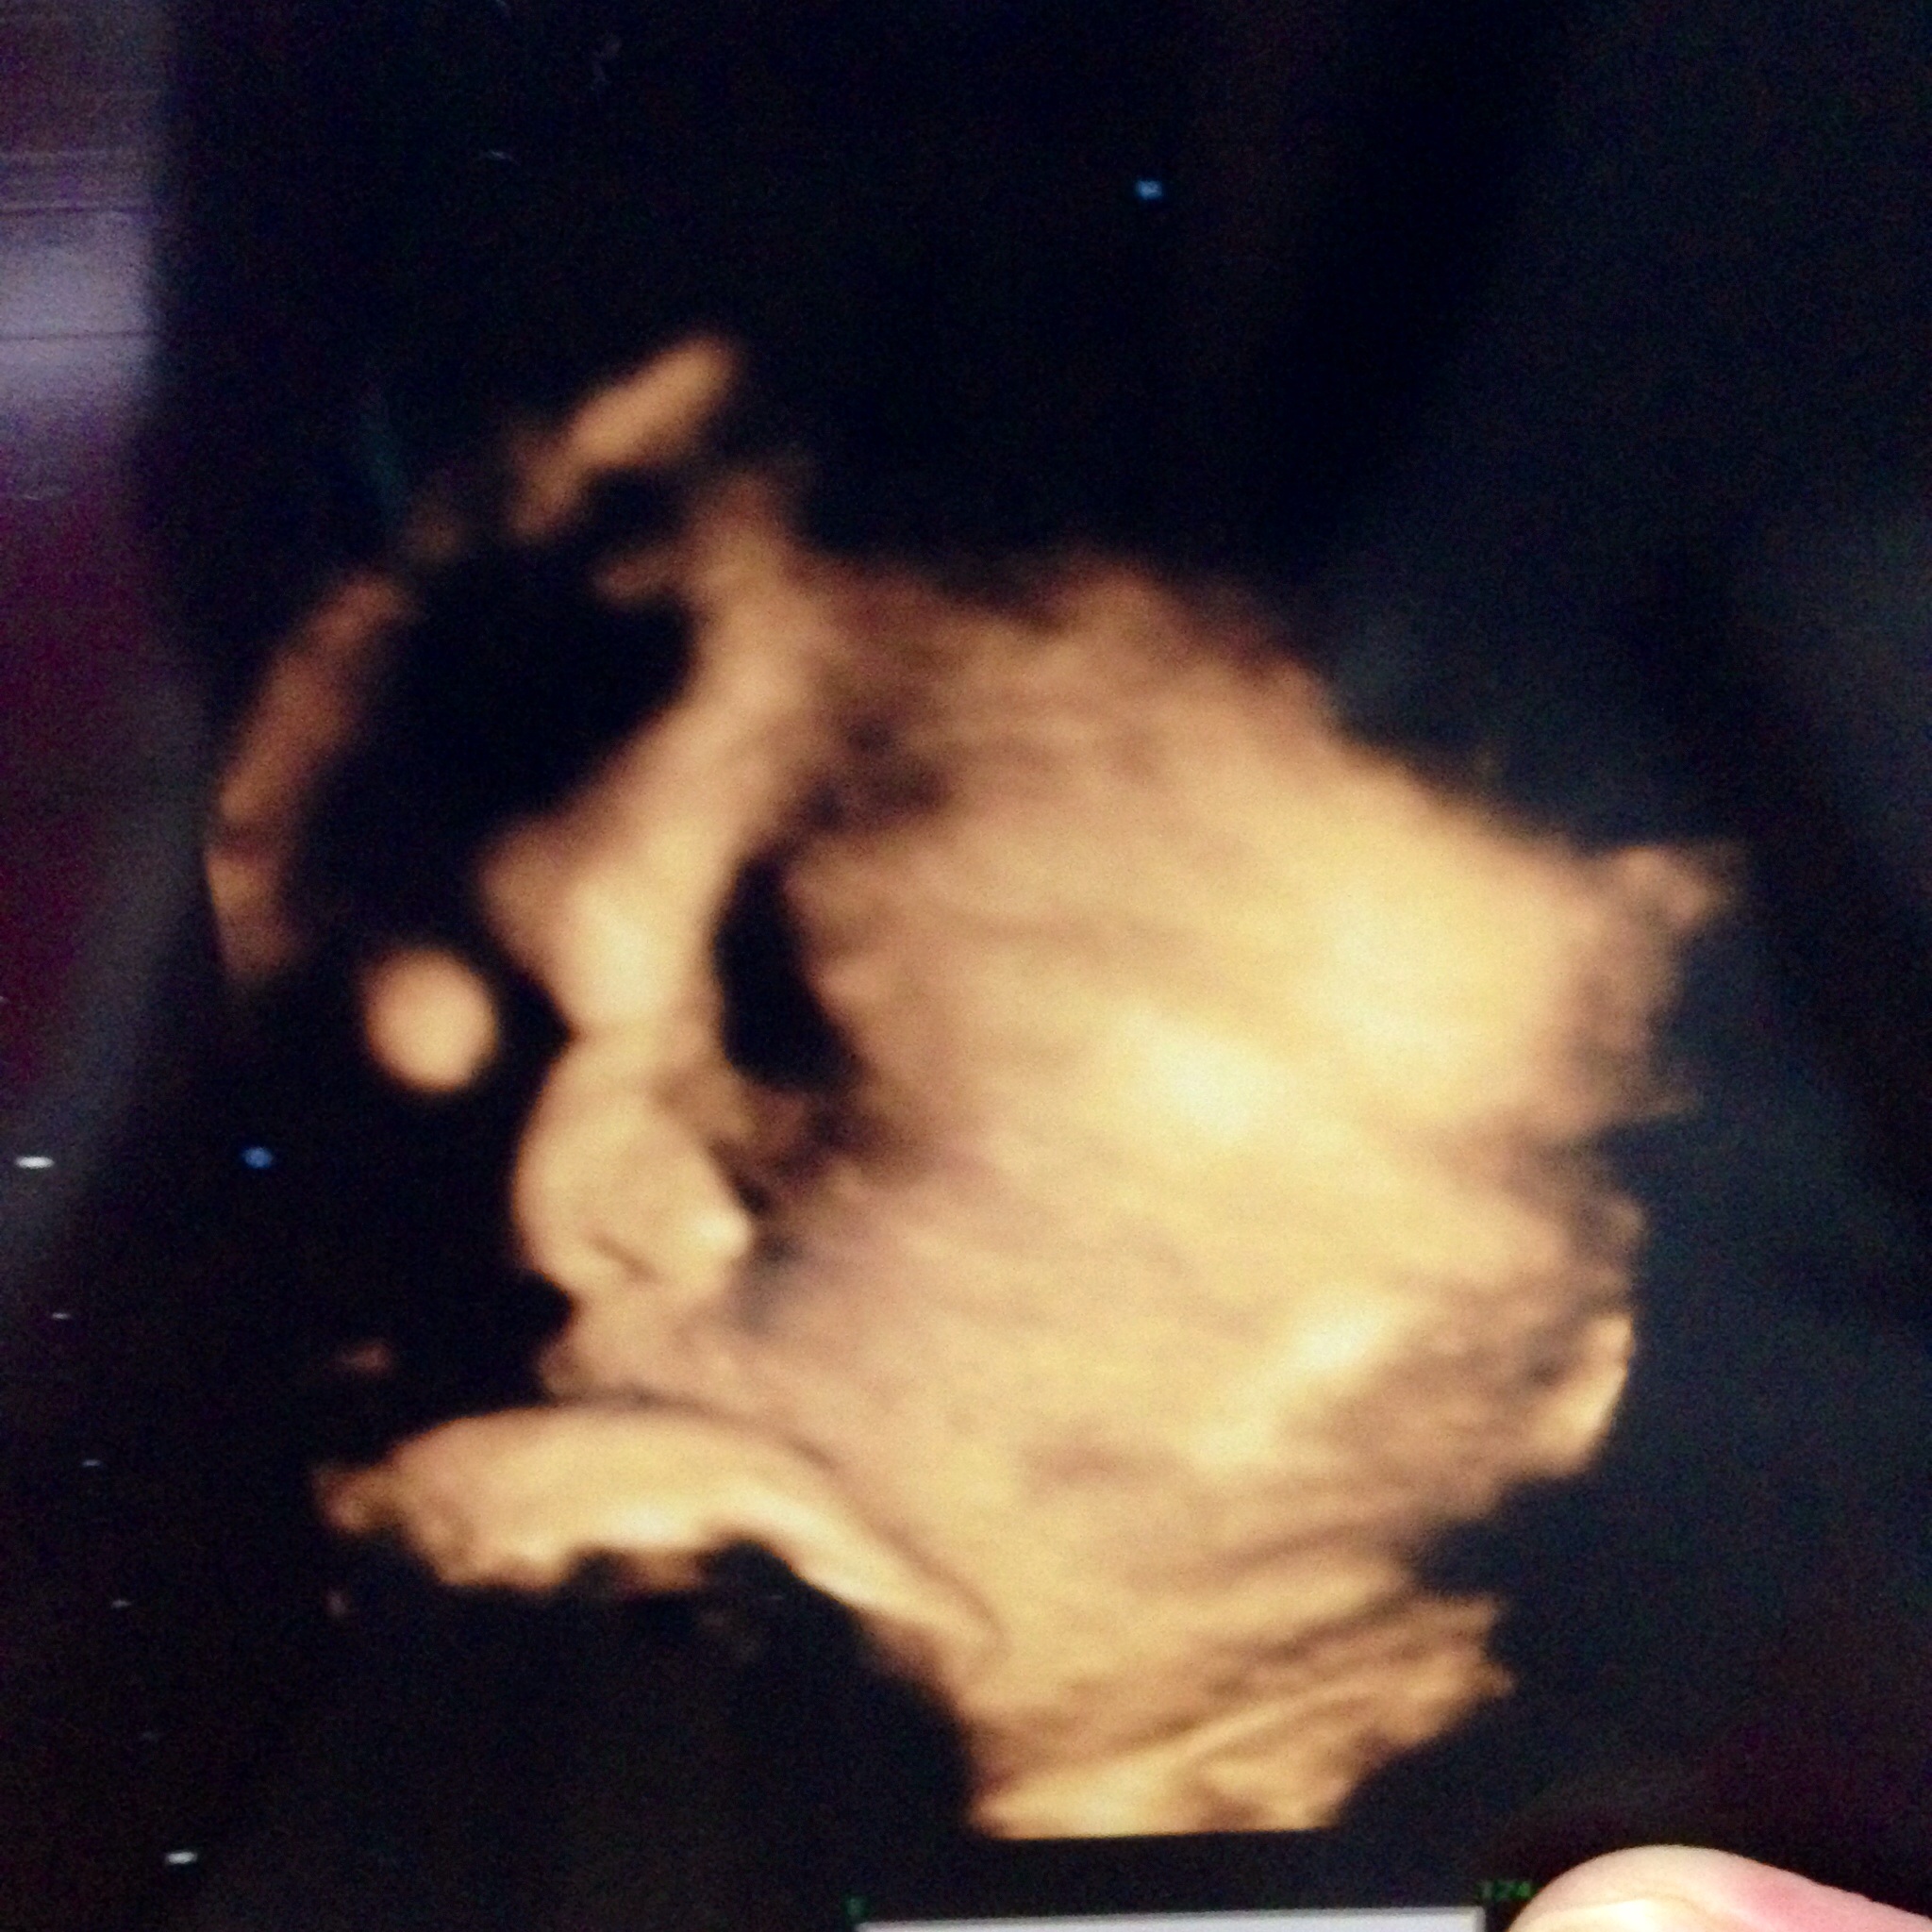

もう上手くエコーに映らなくなってきたよーーぶしゃいく。

推定3021g

あ、この産院には先生が3人いるのですが、前に聞いた先生じゃなかったから、また「うちの子、鼻 高いですよね!」って聞いちゃいました。←しつこい笑